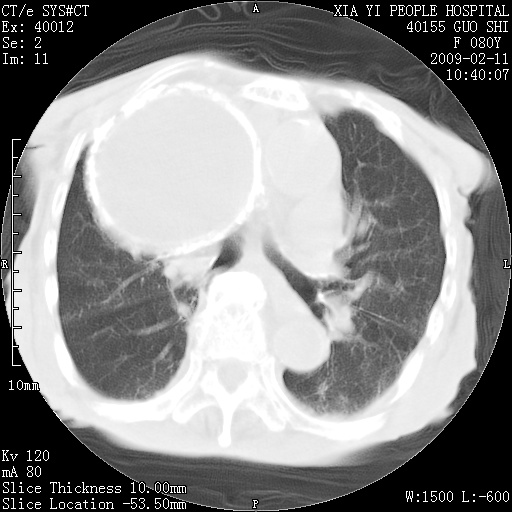

以下是引用随光逐影在2009-2-16 16:34:00的发言:[br]1)考虑右前纵隔皮样囊肿。2)双侧少量胸腔积液。

以下是引用zjzjr在2009-2-16 17:30:00的发言:[br]支持囊性畸胎瘤 双侧少量胸腔积液。